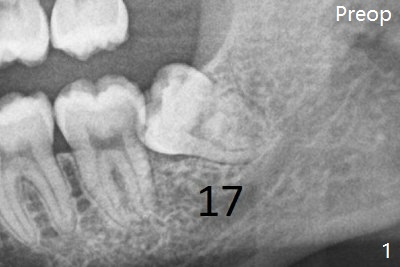

There is bone regeneration 1 year postop (Fig.15,16).